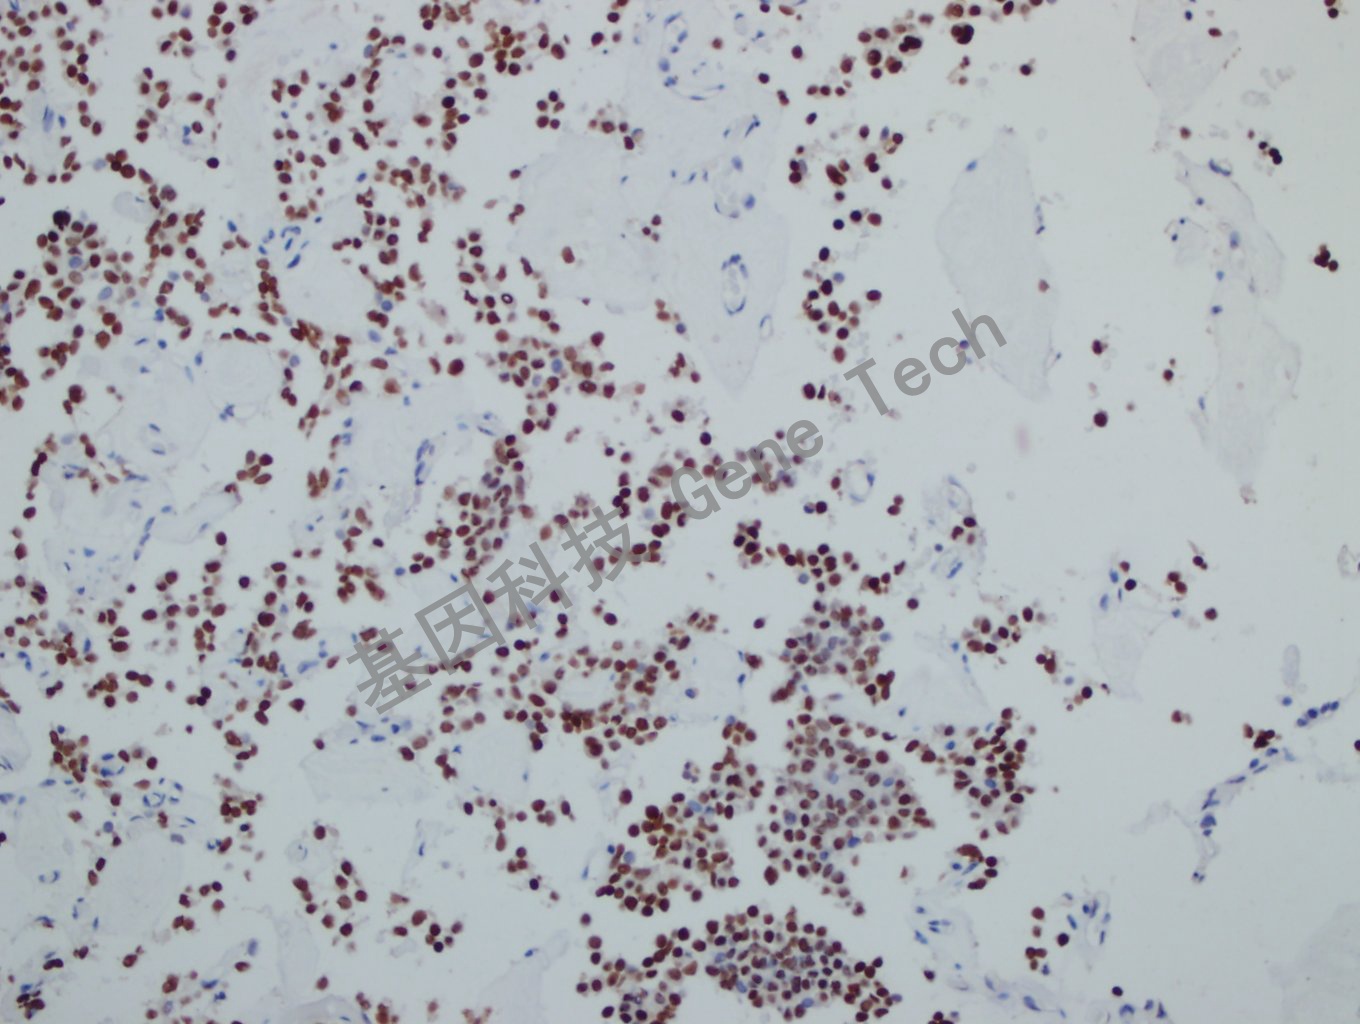

| 預處理:高pH熱修復 | 陽性部位:細胞核 | 陽性對照:垂體瘤 |

| 垂體瘤石蠟切片,用 PIT-1(GT2319)染色,細胞核陽性,DAB 顯色。 | ||